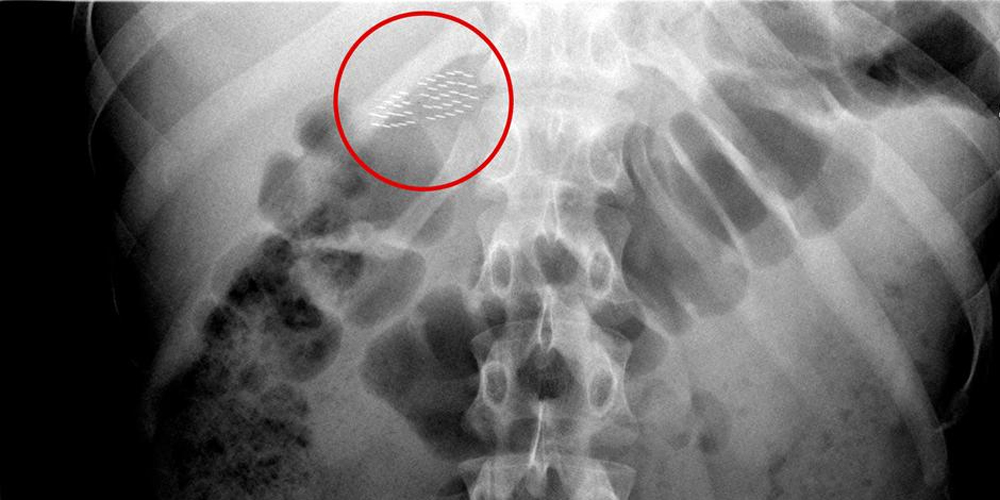

Un equipo médico de la ciudad de Pasighat, India, se encontraron en una particular emergencia médica cuando extrajeron un cepillo de dientes del estómago de un paciente. El hombre se lo había tragado por accidente mientras se lavaba los dientes, según informa Medical Dialogs.

De acuerdo al cirujano Bomni Tayeng, tomó la decisión de realizarle un laparotomía al hombre y retirarle el objeto en una corta intervención que duró 35 minutos. «Fue complicado rastrear el cepillo”, señaló el médico.